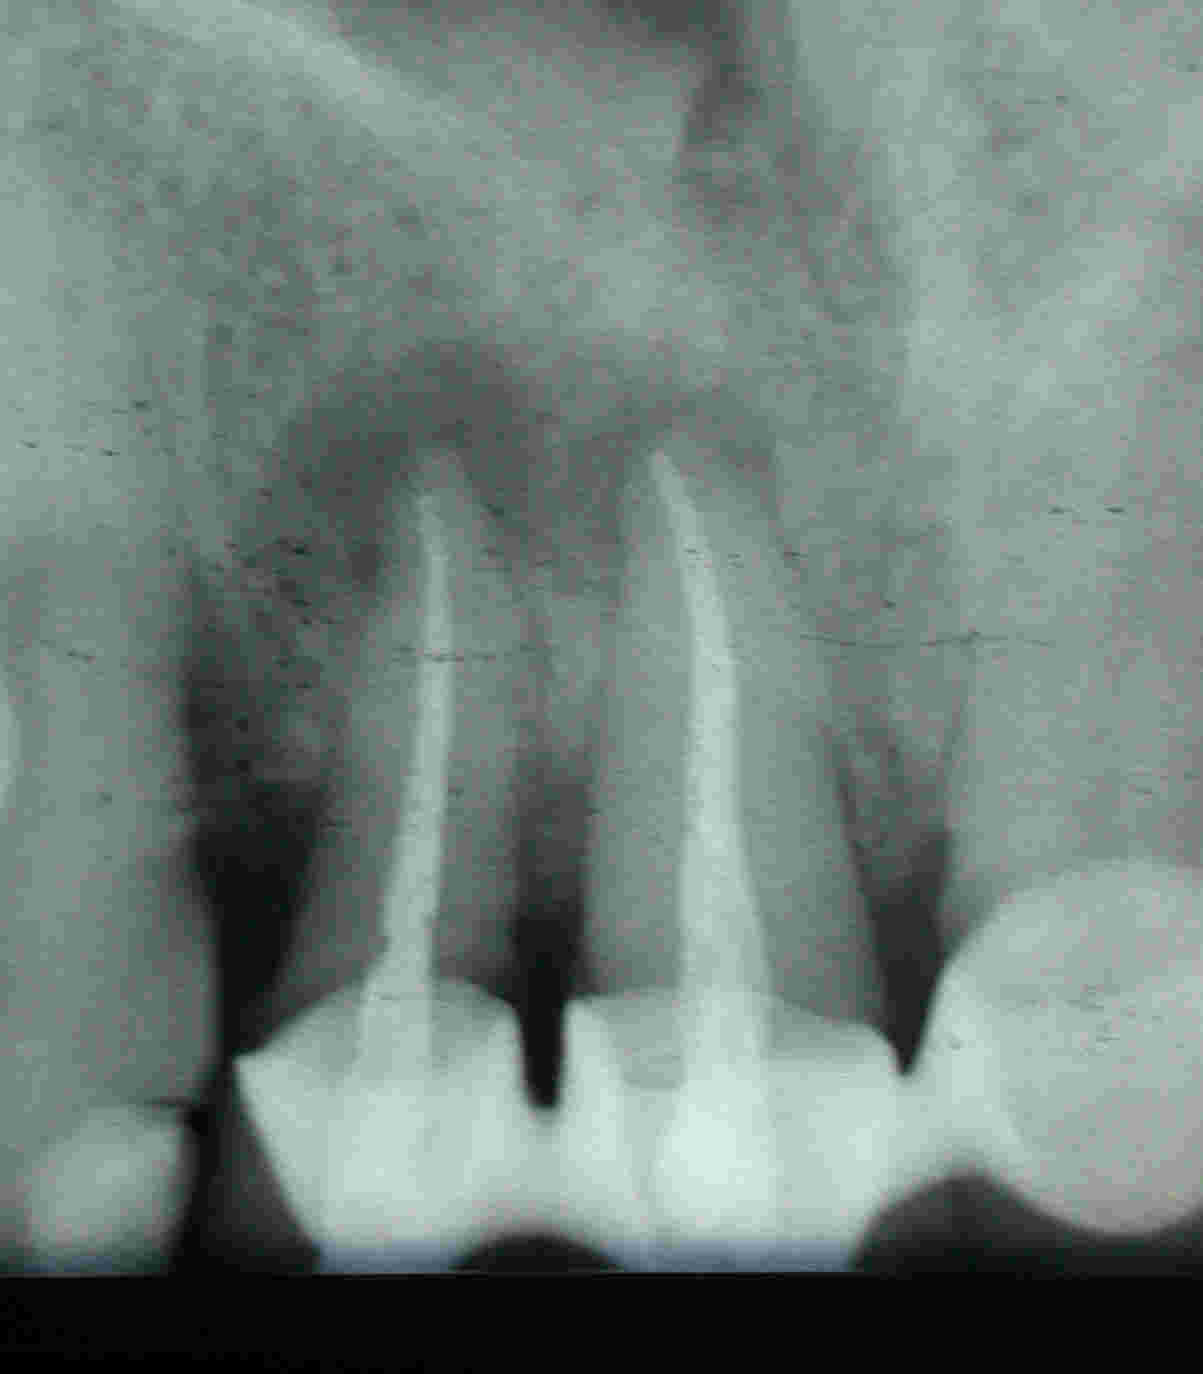

....Wurzelspitzenresektionen eine derart schlechte Prognose haben, wenn man den folgenden Fall einer Gangränbehandlung anschaut, bei der die infizierten Wurzeln in einer Sitzung aufbereitet, abgefüllt und resiziert wurden.

Zustand nach Resektion in gleicher Sitzung (Klick!)

Das hohe Risiko des Scheiterns mit Exazerbation und Fistelbildung in bis zu 50% der Fälle ist darin begründet, dass in solchen Fällen mit Sicherheit nicht nur der Periapex und das apikale Drittel der Wurzeln keimbesiedelt sind, sondern das gesamte endodontische Hohlraumsystem. In der Folge ist es nicht mehr als ein Lotteriespiel, ob in Abhängigkeit von der Qualität der verantwortlichen Bakterien durch die getroffenen Maßnahmen ein Zustand hergestellt wird, mit dem das Immunsystem des individuellen Patienten alleine fertig wird. Denn es muss damit alleine fertig werden. weil der Behandler  das Heft vollständig aus der Hand gibt.

Wenn man dieses überholte, massiv invasive Verfahren schon nicht als Kunst- oder Behandlungsfehler bezeichnen mag, so handelt es sich doch zumindest um eine ausgeprägte Form von Überbehandlung (Overtratment). Dies um so mehr als solch typische, wenig umfangreiche Aufhellungen mit geduldiger Desinfektion nach der Timbuktu-Methode in über 98% der Fälle voraussagbar konservierend ausgeheilt werden können.